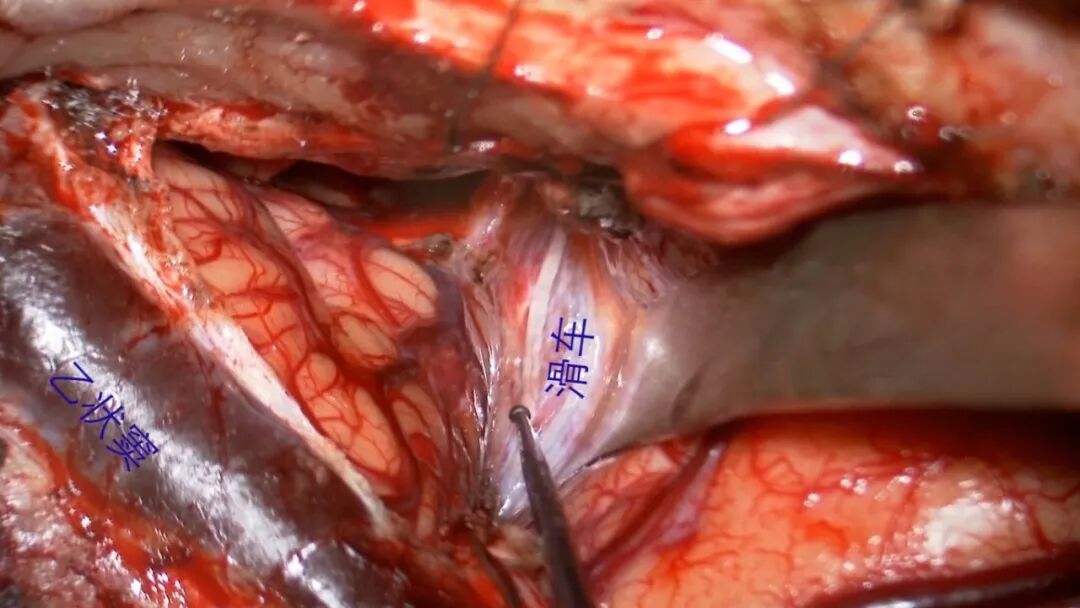

分离外展神经

分离内听动脉

分离基底动脉

滑车神经 乙状窦

三叉神经

外展神经

面听神经

后组神经

椎动脉

基底动脉

小脑前下动脉

纯熟的显微外科操作技巧在岩斜区脑膜瘤手术中尤为重要。显微操作的要点为锐性分离。以显微剪刀为主的锐性分离可最大程度保留肿瘤与神经组织之间的蛛网膜界面,可避免盲目牵拉所致的穿支血管断裂或神经功能损伤。辨认并保持肿瘤与脑组织界面可提高分离效率,事半功倍。

本例外展神经被肿瘤包裹其中,先在外展神经进入斜坡硬膜处锐性分离,此处神经位置固定容易辨认,然后顺势分离外展神经脑池段,最后使其完整保留。本例肿瘤与脑干腹侧静脉之间的分离、内听动脉的分离、基底动脉的分离均采用显微剪刀锐性分离,使得创伤尽可能小。岩斜脑膜瘤常包绕基底动脉及桥脑穿支血管,分离至斜坡方向时应格外小心,避免灾难性后果。